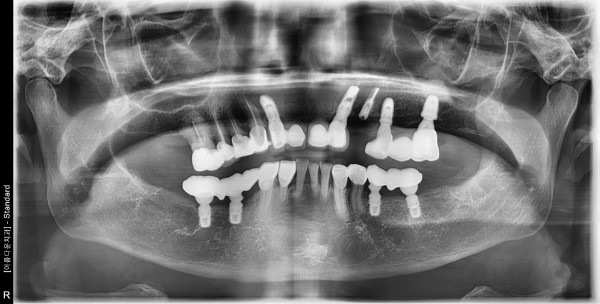

67세 여자 상악 뼈 이식후 임플란트 식립